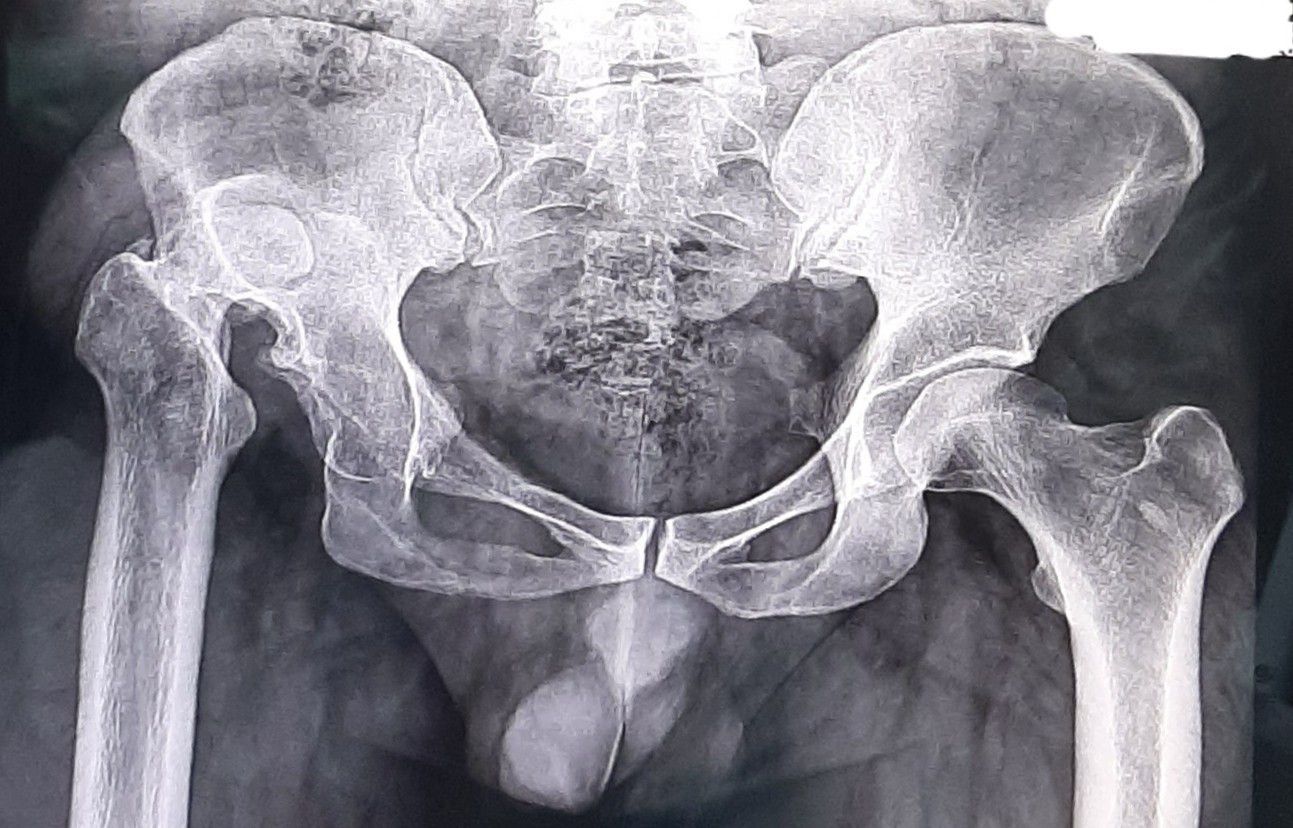

What's your diagnosis ^ _ ^

Developmental dysplasia of the hip (DDH) is a problem with the way a baby's hip joint forms. Sometimes the condition starts before the baby is born, and sometimes it happens after birth, as the child grows. It can affect one hip or both.